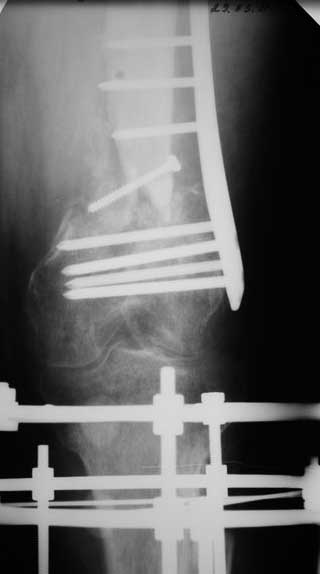

Уважаемые коллеги. Хотелось бы услышать Ваше мнение по следующему случаю. На лечении в отделении находится пациент 45 лет. С диагнозом: Замедленно консолидирующийся надмыщелковый перелом левой бедренной кости фиксированный пластиной от 06.12.10. Ложный сустав большеберцовой кости левой голени фиксированный АНФ от 06.12.10.

Стойкая контрактура левого коленного, голеностопного суставов. Укорочение левой нижней конечности на 5 см. Обширные кожные рубцы верхней трети левой голени. Хроническая венозная недостаточность левой нижней конечности.

Анамнез: травма 18.06.10 в результате ДТП, водитель. Диагноз: Сочетанная травма головы, конечностей. ЗЧМТ. Сотрясение головного мозга. Открытый многооскольчатый внутрисуставной перелом мыщелков и нижней трети левой бедренной кости со смещением отломков. Открытый перелом костей левой голени в верхней трети со смещением отломков. Обширные рвано – ушибленные раны левого бедра, верхней трети левой голени. Находился на лечении в нескольких стационарах, где проводились оперативные вмешательства.

7. 06.12.2010г. Открытая репозиция, остеосинтез чрезмыщеково – надмыщелкого перелома левой бедренной кости пластиной со свободной костной пластикой из гребня левой подвздошной кости (во время операции из за сомнений в жизнеспособности костного отломка перелома бедра произведено его удаление. За счет чего образовался дефект костной ткани и укорочение левого бедра на 5,0 см; Мыщелки бедра были в сгибание, 5 месяцев нога не опорная, при попытке их репонировать крошились , зафиксировали как стояли. Остеосинтез переломов костей левой голени в АНФ.

Местно: Ходит при помощи костылей с попыткой полной нагрузки на левую ногу. Левый коленный сустав в положении разгибания. Движения в коленном суставе качательные. Воспалительных явлений области послеоперационных рубцов, мест выхода спиц нет. Анализы крови без воспалительной реакции.

Голень: выполнить остеосинтез левой большеберцовой кости интрамедуллярным стержнем с рассверливанием. На основании боковой рентгенограммы коленного сустава мыщелки бедра в сгибании, голень в переднем подвывихе, создается впечатление, что удастся завести стержень при такой контрактуре, или выполнить отсечение бугристости, попытаться согнуть колено и заштифтовать. Есть ли опыт штифтования при стойких контрактурах?

Бедро, коленный сустав: через 1 месяц срединным доступом с отсечение бугристости большеберцовой кости произвести реостеосинтез надмыщелкого перелома бедра с выведением мыщелков из сгибания. Коленный сустав: мобилизация головок четырехглавой мышцы бедра, артролиз, редрессация. Вопрос: на таком сроке – получиться ли одномоментно вывести мыщелки из сгибания или необходимы аппаратные способы устранения положения мыщелков?